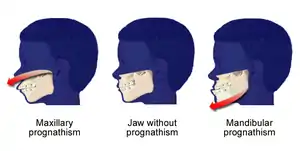

| Mandibular Prognathism Development Pattern in Tricho Dento Osseous Syndrome | |

| |

| Shows the severe underbite pattern that is a common development pattern in individuals with Tricho Dento Osseous Syndrome | |

Tricho–dento–osseous syndrome (TDO) is a rare, systemic, autosomal dominant genetic disorder that causes defects in hair, teeth, and bones respectively. This disease is present at birth. TDO has been shown to occur in areas of close geographic proximity and within families; most recent documented cases are in Virginia, Tennessee, and North Carolina. The cause of this disease is a mutation in the DLX3 (distal-less 3) gene, which controls hair follicle differentiation and induction of bone formation. One-hundred percent of patients with TDO suffer from two co-existing conditions called enamel hypoplasia and taurodontism in which the abnormal growth patterns of the teeth result in severe external and internal defects.[1] The hair defects are characterized as being rough, course, with profuse shedding. Hair is curly and kinky at infancy but later straightens. Dental defects are characterized by dark-yellow/brownish colored teeth, thin and/or possibly pitted enamel, that is malformed. The teeth can also look normal in color, but also have a physical impression of extreme fragility and thinness in appearance. Additionally, severe underbites where the top and bottom teeth fail to correctly align may be present; it is common for the affected individual to have a larger, more pronounced lower jaw and longer bones. The physical deformities that TDO causes become more noticeable with age, and emotional support for the family as well as the affected individual is frequently recommended. Adequate treatment for TDO is a team based approach, mostly involving physical therapists, dentists, and oromaxillofacial surgeons. Genetic counseling is also recommended.

In the oral cavity 100% of people diagnosed with TDO have taurodontism which is characterized by vertically enlarged pulp chambers at the expense of the roots of the teeth; the floor of the pulp chamber and furcation is moved apically down.[1] This is due to the failure of the Hertwig epithelial root sheath which maps the shape of the forming tooth roots during active differentiation. Amelogenesis imperfecta, an abnormal formation of the enamel or external layer of the crown of the tooth, may also be present where the tooth enamel may be thin or absent. There are several clinical subsets of amelogenesis imperfecta, but common to TDO is the hypoplastic-hypomaturation subtype;[3] the hypomaturation-hypoplastic is less common in individuals with TDO. The difference between the 2 dominant subtypes is the changes seen in the enamel matrix, and the phenotypic type that predominates. The hypoplastic-hypomaturation type of amelogenesis imperfecta with TDO occurs where the tooth enamel depicts a generalized pitted pattern, with open contacts between the teeth as well as an open bite. A smaller number of cases are of the hypomaturation-hypoplastic case type, in which the enamel structure is softer due to the under maturation of ameloblasts during development. Mandibular prognathism also called a severe underbite, is also a prominent feature in TDO. Prognathism defects are diagnosed based the level of severity that this condition interferes with being able to chew or speak properly.